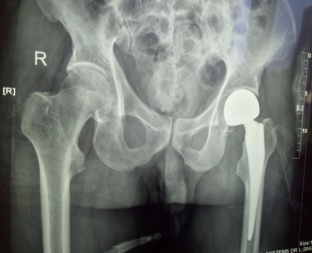

患者張XX,男,75歲,6月前腦梗塞遺留左側(cè)肢體偏癱,合并高血壓、糖尿病。